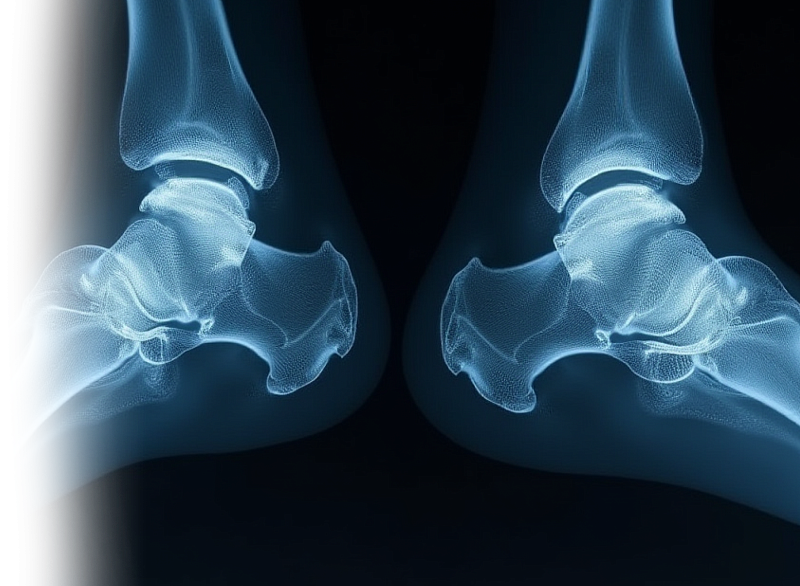

При одновременном сканировании КТ позволяет сравнить два смежных сустава, а также исключить патологию сустава костно-травматического, дегенеративного характера, изменения опухолевого или воспалительного генеза.

Показания для проведения КТ двух смежных суставов:

- травма, боль, отек в области сустава/суставов.

Также оцениваются окружающие сустав мягкие ткани (для более детальной оценки мягких тканей целесообразно МР-исследование суставов).